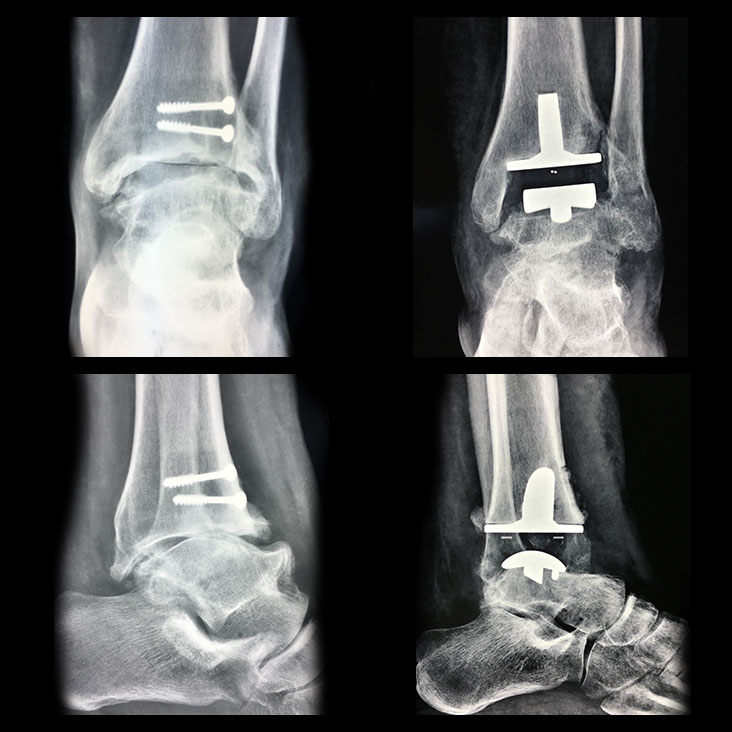

Radiografia in movimento

La radiografia in movimento mostra lo spazio articolare ripristinato e la distanza tra tibia e astragalo. Il movimento risulta fluido e scorrevole, simile a quello fisiologico. Il risultato che si deve ottenere al termine dell’intervento di Protesi di Caviglia è la normale mobilità della caviglia in flesso-estensione.

Il protocollo post-operatorio stabilisce che si deve fare una RX dopo un mese, una RX dopo 3 mesi, un’altra dopo 6 mesi e ogni anno successivo all’intervento. Solo così si può controllare la compatibilità dell’impianto con l’organismo.